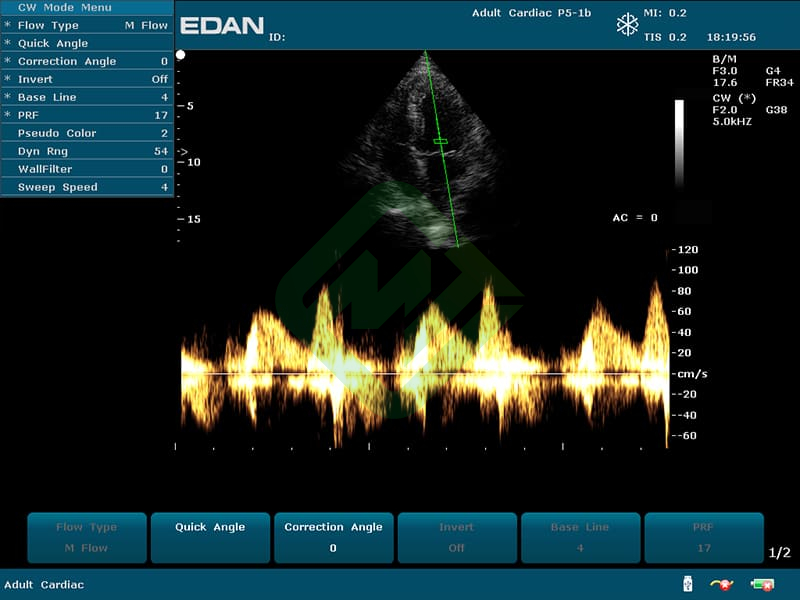

- Режимы сканирования: B, M, CDI, PW, CW, PDI, DPDI или B, M, ЦДК

- Доплерография: импульсно- и постоянно-волновая, направленная энергетическая

— мультичастотные УЗ-датчики: линейный датчик Edan L742UB, конвексный датчик Edan C352UB, фазированный датчик Edan P5-1b

— цветовое доплеровское картирование

— импульсно- и постоянно-волновая доплерография

— фазированным P5-1b: частотный диапазон датчика 1,8–4,3 МГц, угол обзора 90°, глубина сканирования 320 мм, количество элементов 64 - Также для U50 подходят датчики (приобретаются отдельно):

- Датчик фазированный ультразвуковой P5-1b — 1 шт.